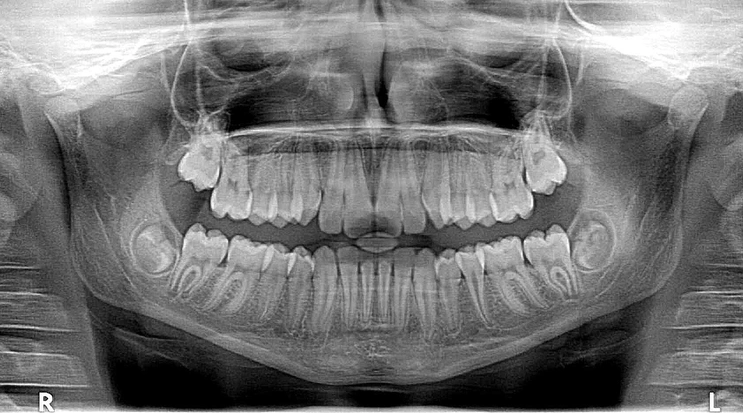

어금니 크라운 치료는 여러 단계로 이루어지며, 각 단계마다 세심한 주의가 필요합니다. 첫 번째 단계는 진단입니다. 치과 의사는 엑스레이 검사 및 기타 진단 방법을 통해 손상된 부위를 확인합니다. 이후, 치료 계획을 세우고 환자와 상담하여 최적의 치료 방법을 제시합니다.

- 진단: 엑스레이 및 구강 검진을 통해 치아 상태를 평가합니다.